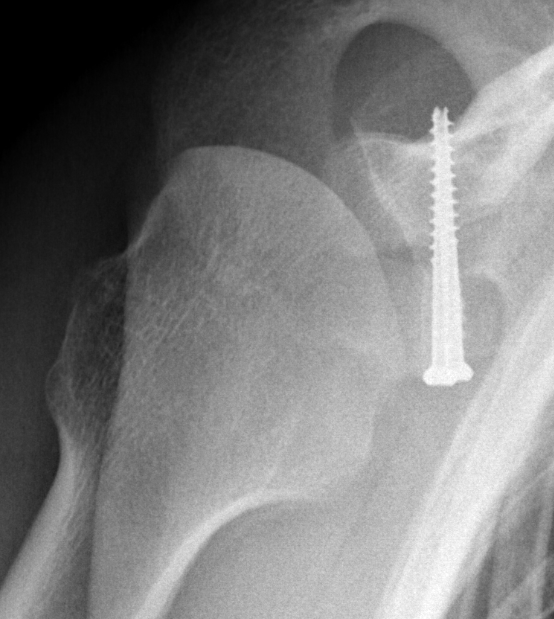

Case 2: Large glenoid defect